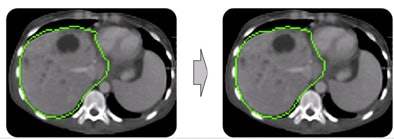

To correct a mistake in segmentation, the user simply draws in the correction as a 2D contour that defines the actual border of the object in one slice, Heckel said.

An extrapolation process is performed using a live-wire segmentation algorithm, which automatically moves the user-drawn contour to adjacent slices. The algorithm accomplishes this by moving equidistant seed points on the contour to the adjacent slice using a 2D block-matching algorithm.

| Step one (above) requires the user to simply draw the actual border of the liver in one slice. The extrapolation of this user contour extracts equidistant seed points, connects seed points using a live-wire segmentation algorithm, and replaces part of the initial contour. Below, the user contour is extrapolated to neighboring slices for 3D correction. A search for seed points is performed in a given search area using a block matching algorithm. The seed points are connected using the live-wire algorithm, and this process continues until termination criteria are met. |